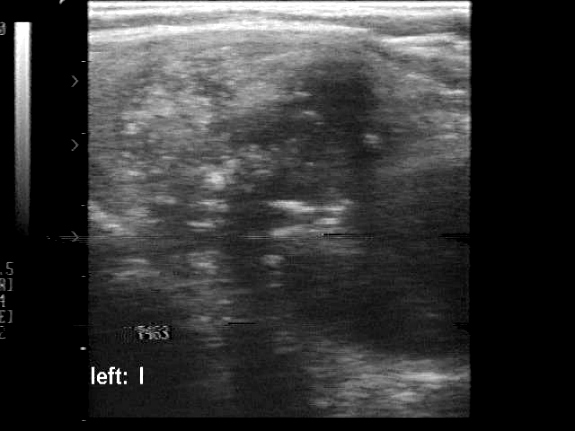

Medullary carcinoma (histological diagnosis) - case 529

A metastatic lymph node is presented in this case. The node has at least four hyperechogenic patches on the left in the horizontal scan. These have an echonormal background and display small hyperechogenic granules. There is acoustic shadow in the right in the longitudinal view.